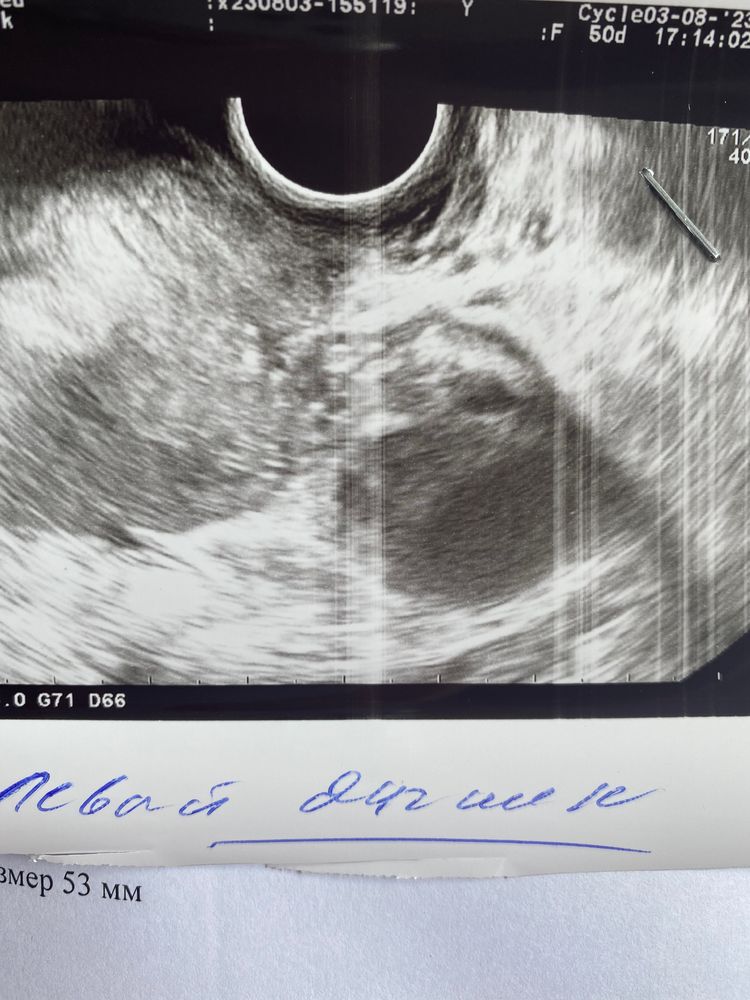

Позавчера было узи у моего гинеколога, эндометрий 9.7 доминантный фолликул 20 мм. После чего был укол хгч 10000. Позавчера! Пришла сегодня на узи ( тот же самый аппарат) другой узист (моя в отпуск ушла) она мне сказала, что ДФ=18 и эндометрий всего 6! Я могу предположить, что фолликул сдулся, но куда делся эндометрий? И кто-то понимает по картинкам, может, это ЖТ? А не фолликул?

Больше похоже на формирующееся ЖТ, почти нет анэхогенности, значит и жидкости. Даже если он сдулся - куда делась жидкость? А вообще у меня так обычно выглядит регресс ЖТ, оставшегося от прошлого цикла. А по замерам - вот давно замечала, что у разных специалистов у меня разная толщина эндика)

Похоже на жт больше, так как часть содержимого анэхогенное, а эндик ну может так померкла просто коряво)

Похоже на фолликул все таки, четкий ровный круг с контурами